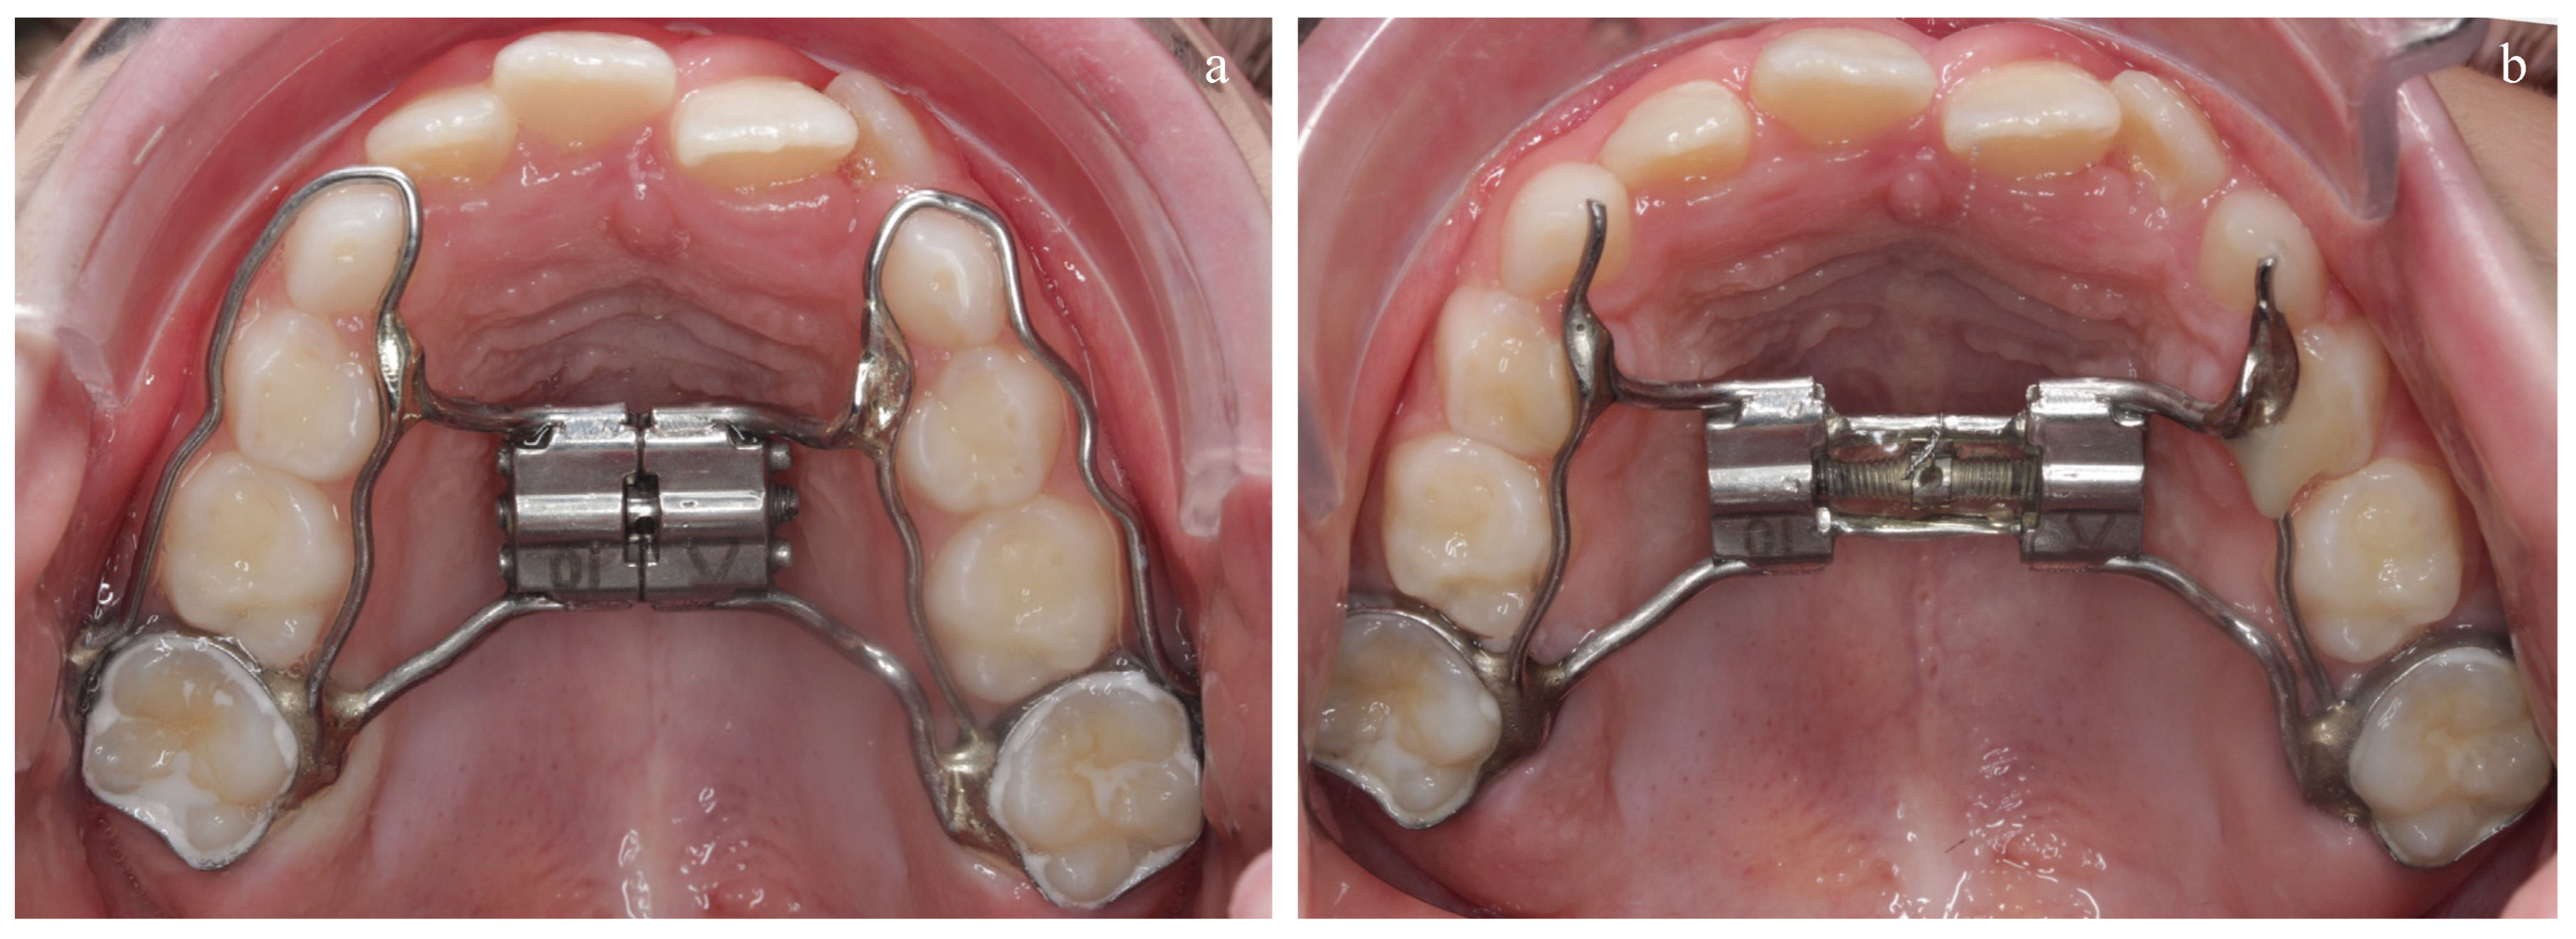

| Narrow palatal arch | Narrower maxillary arch [11] Palatal crossbite and reduced transverse maxillary width [18] | Yap et al. Katyal et al. | 2019 2013 | Case–control Case–control | |